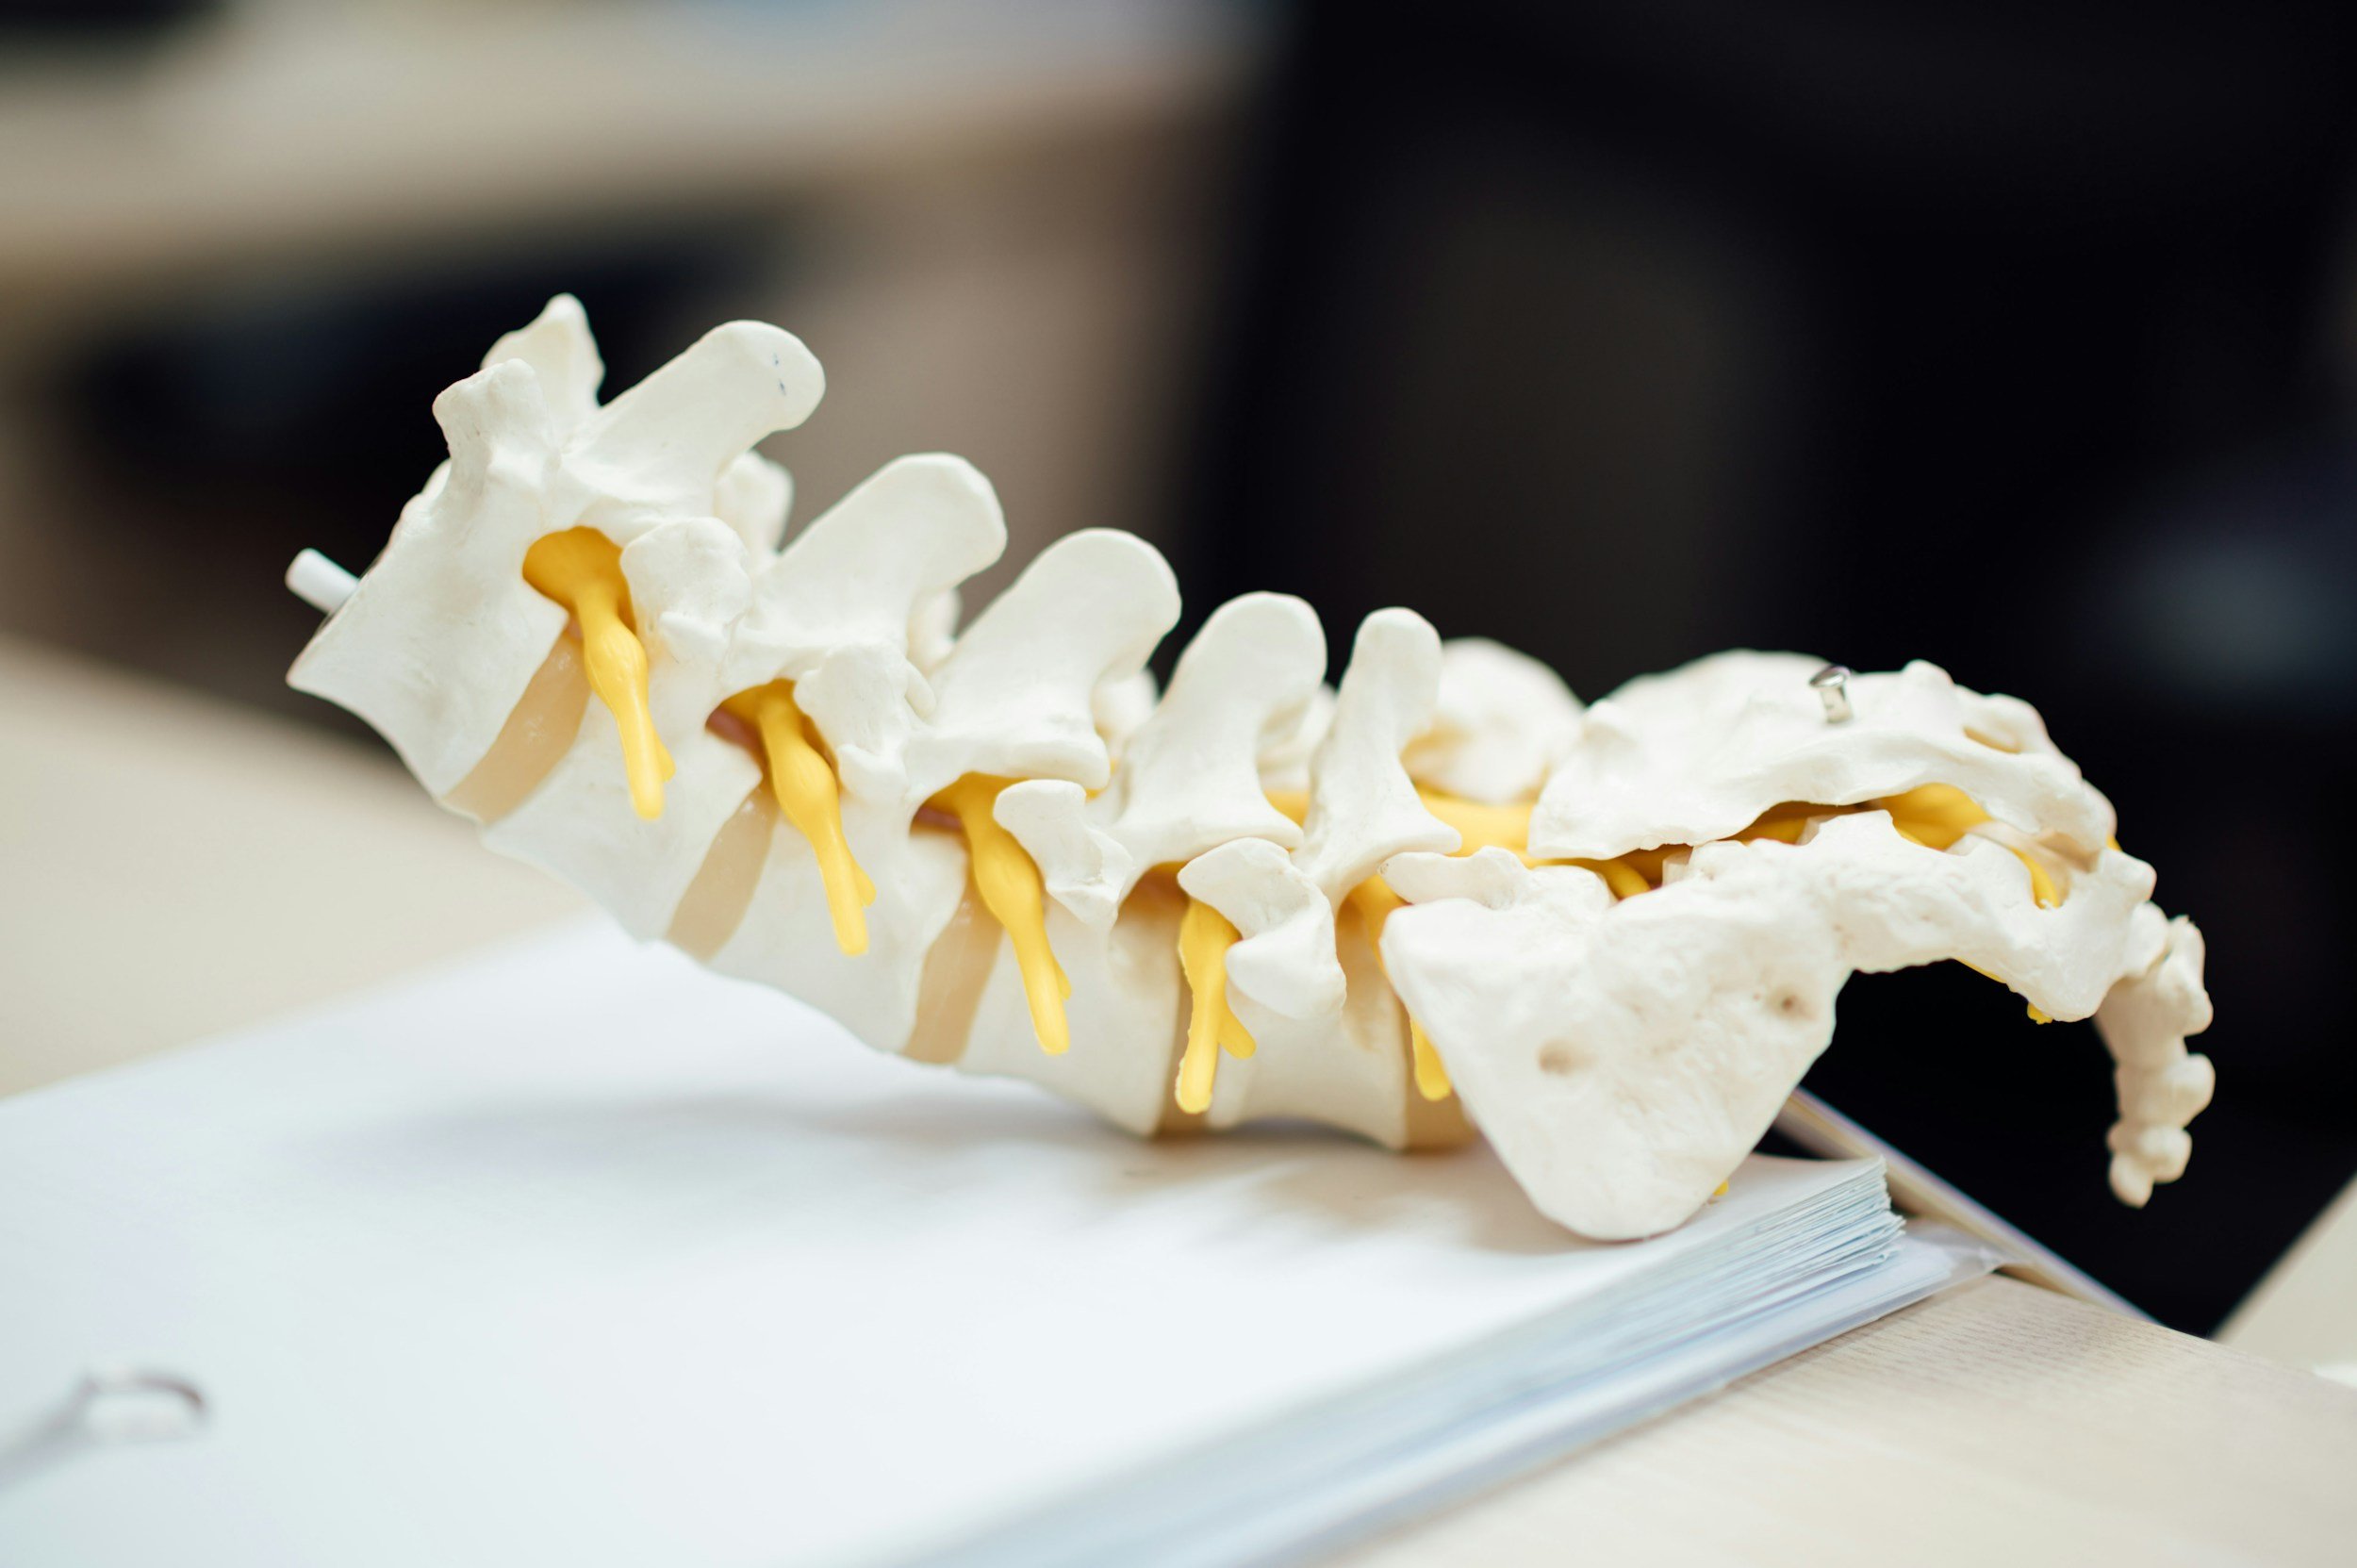

Lumbar Spondylolisthesis

Chris Daly

Chris Daly is a consultant neurosurgeon at the Gold Coast University Hospital and Gold Coast Private Hospital. He completed fellowship training in spine surgery in Vancouver, Canada. He holds a PhD from Monash University, investigating the use of adult stem cells in the treatment of lumbar degenerative disease. Here he discusses his approach to the management of lumbar spondylolisthesis.